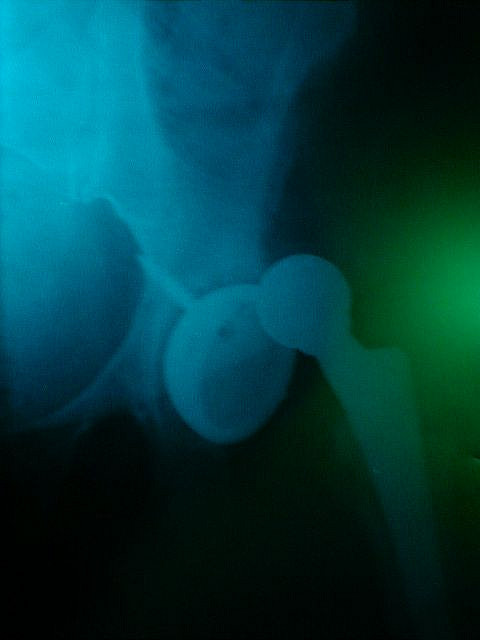

The BBC ran an interesting story the other day about hip fractures.

Apparently 78,000 people suffer from a hip fracture every year in the UK; 10% of these people will be dead within 30 days, 30% will be dead within a year, and half are left with permanent disability.

NICE, the National Institute for Health and Clinical Excellence, advises same day hip operations for fractures as this significantly improves on this desperate performance.

Image by Cindy Funk